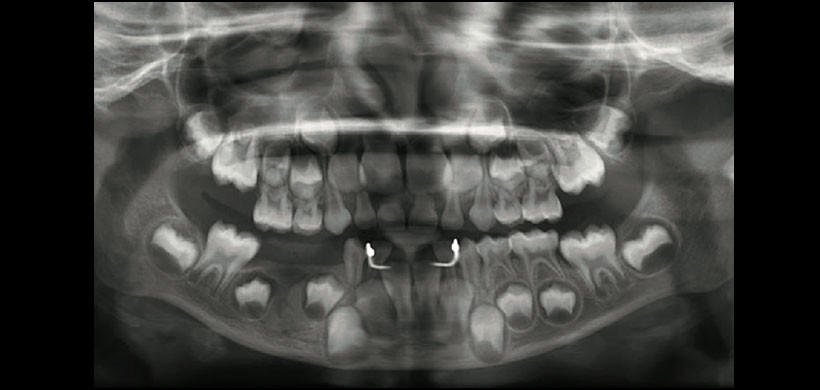

Figura 4: Radiografía panorámica post operatorio a los 6 meses, no se evidencia recurrencia.